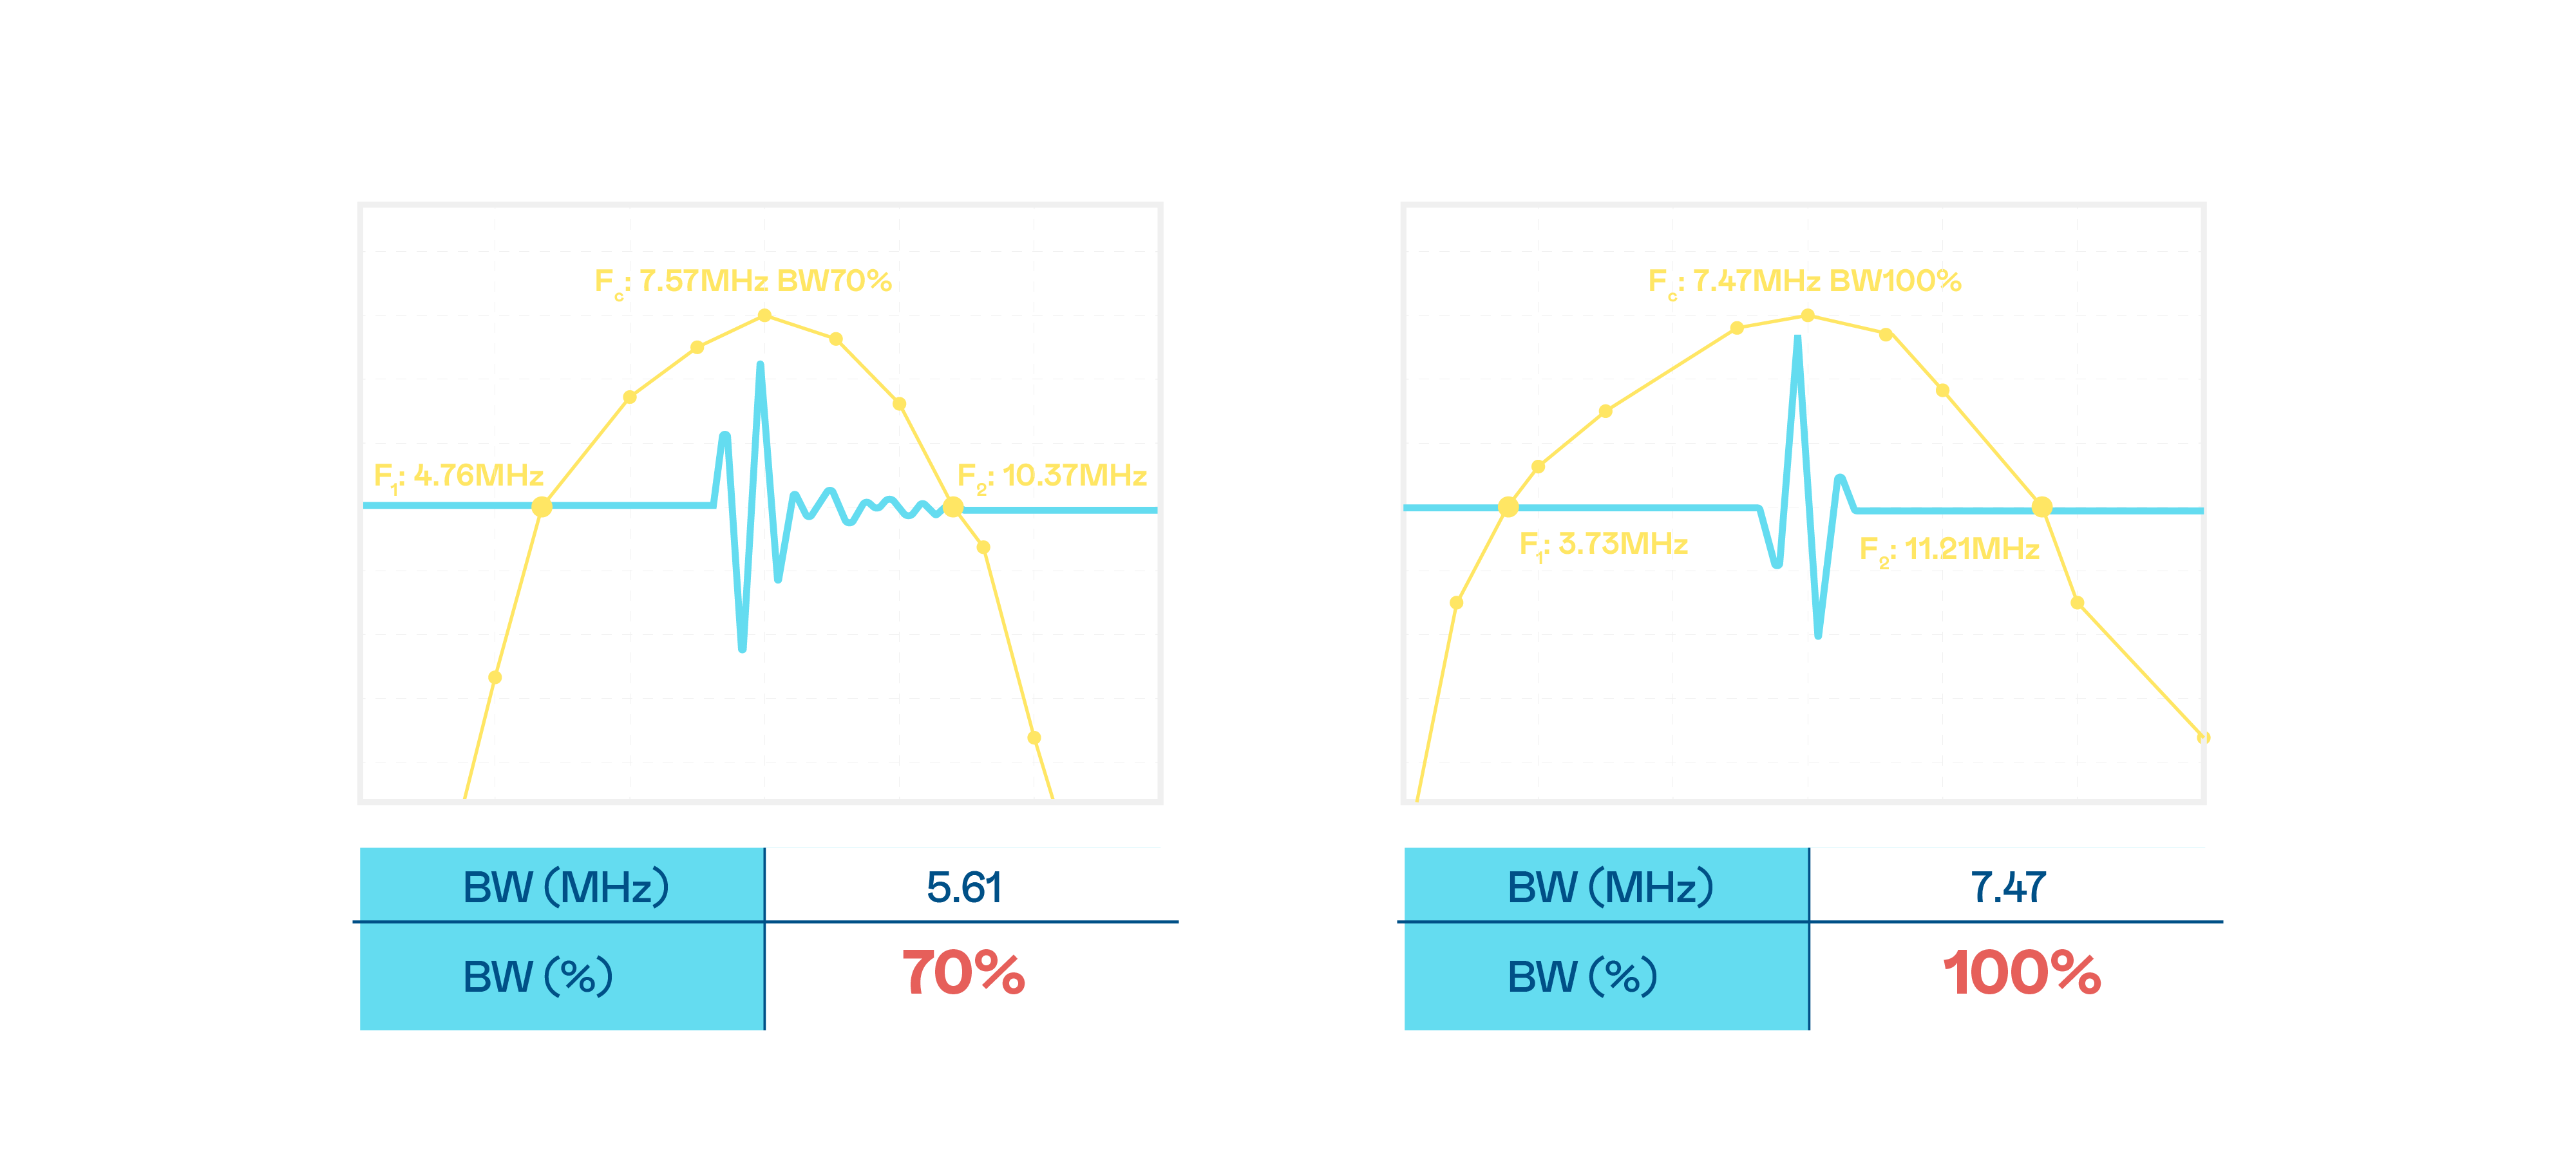

CMUT technology utilizes capacitive MEMS components to generate ultrasound signals. Compared to traditional ceramic piezoelectric technology, the 30% increased bandwidth of CMUT allows for wider ultrasound signals and greatly improved image resolution. This is a crucial technology for achieving medical ultrasounds with high-quality images and promoting the development of precision medicine.

Ultra-wide bandwidth offers high-quality images

The image quality of medical ultrasound depends on the signal bandwidth the ultrasound transducer can emit. AUO's CMUT offers high-resolution ultrasound signals with ultra-wide bandwidth and high sensitivity for more delicate image texture and details to help ultrasound medical examiners reduce time on interpreting and diagnosing based on precise medical images.